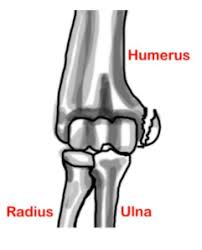

Medial epicondyle fractures represent almost all epicondyle fractures and occur when there is avulsion of the medial epicondyle. They are typically seen in children, and can be challenging to identify. Ligaments connect bones to other bones. Random house webster's unabridged english dictionary. It is amazing when the importance of the small parts, mostly unrecognized things, of the living world is considered. From wikipedia, the free encyclopedia. It is larger and more prominent than the lateral epicondyle and is directed slightly more. The epicondyle is something similar to the condyle but is present on the outer surface on top of the condyle, it does not have any direct connection there are many epicondyles present in a human body, and they have different characteristics. Example sentences from the web for epicondyle. The medial epicondyle of the femur is an epicondyle, a bony protrusion, located on the medial side of the femur at its distal end. 16% calcification along lateral epicondyle 19. From wikipedia, the free encyclopedia. There are various epicondyles in the human skeleton, each named by its anatomic site.

Random house webster's unabridged english dictionary. There are various epicondyles in the human skeleton, each named by its anatomic site. An epicondyle is a rounded eminence on a bone that lies upon a condyle. A part that sticks out at the end of a bone, often where muscles and tendons are attached: Cranial to the medial epicondyle, the median nerve passes between the origins of the pronator teres and biceps brachii muscles. Located on the largest breadth above the medial and lateral meniscus. Epicondyle synonyms, epicondyle pronunciation, epicondyle translation, english dictionary definition of epicondyle. The epicondyle is one factor similar to the condyle nevertheless is present on the outer flooring on excessive of the condyle, it would not have. If the symptoms are related to a neck problem, an mri scan may be ordered. Both medial and lateral epicondyles can be identified in femur and. Larger skeletal muscles attach to the bones via a tendon. Epicondyle definition, a rounded protuberance at the end of a bone, serving as a place of attachment for ligaments, tendons, and muscles. In birds, where the arm is somewhat rotated compared to other tetrapods, it is called ventral epicondyle of the humerus.

If the symptoms are related to a neck problem, an mri scan may be ordered. A rounded projection at the end of a bone, located on or above a condyle and usually serving as a place of attachment for ligaments and tendons. They are typically seen in children, and can be challenging to identify. Epicondyle refers to a protuberance on the condyle of a long bone. 16% calcification along lateral epicondyle 19.